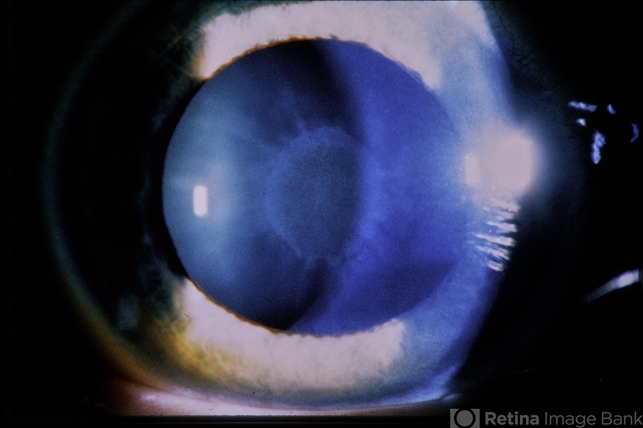

- Wilsons

- Kayser-Fleischer ring

- Kayser-Fleischer ring (copper deposition in Decemet's membrane in the peripheral cornea).